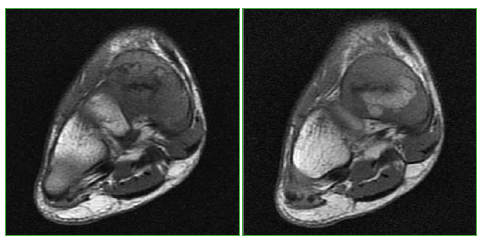

Figura 7.

Resonancia magnética, plano coronal, en secuencia T1. Se visualizan los mismos hallazgos en el pie derecho.

Figura 8.

Resonancia magnética, plano axial, secuencia T1. Se visualizan los mismos hallazgos en el pie derecho.